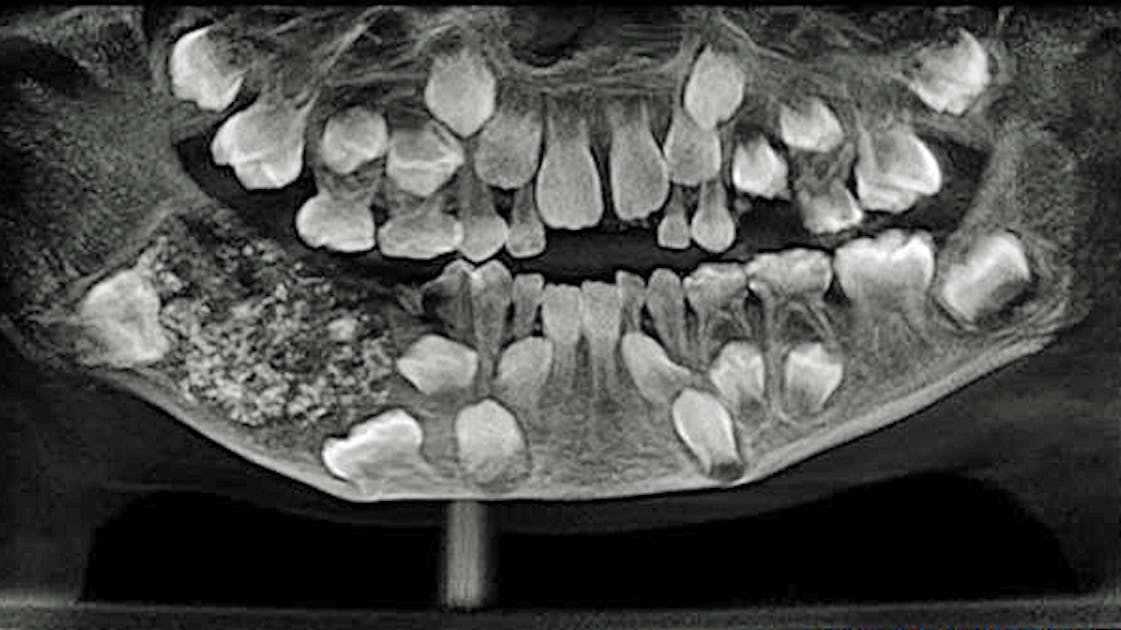

Neue Zähne nachwachsen lassen Die Experten der Dr Jung Zahnklinik informieren über ein Zukunftsthema In einigen Jahren könnten Zahnlücken vieler Menschen durch echte, neue Zähne gefüllt werden Eine neue Technik, welche bei Tieren schon funktioniert, könnte die Lösung sein. Zähne wachsen nicht Zähne wachsen nicht mit 32 Zähne, wie sie der Erwachsene hat, würden im Kindergebiss gar keinen Platz finden Erst nach und nach wächst der Kiefer Beim Schulkind kommen zusätzliche Backenzähne hinzu Das Gebiss umfasst nun schon 24 Zähne. Bei mir wurden heute 5 Zähne gezogen (1 Milchzahn und 4 Bleibende) aber unten bei der Wunde wachsen Zähne nach obwohl alle mit Wurzel gezogen wurden sind, Ich bin 25 Wochen zu früh geboren und habe sehr sehr zu viele Zähne im Mund, weshalb die 5 mir ja auch heute gezogen wurden sind, aber das ist so komisch, ich hab Angst das wenn die mir den wieder enfernen das danach wieder welche Wachsen.

Dem Menschen wachsen zwei komplette Sätze Zähne zunächst die Milchzähne, danach die bleibenden Das bedeutet, jeder gezogene Zahn kann nur durch künstliches Material ersetzt werden Alligatoren haben es da besser. Menschliche Zähne, besonders in einem frühen Alter, sind oft verschiedenen Problemen, Abweichungen von der normalen Entwicklung und Krankheiten ausgesetzt Unter den dentoalveolaren Anomalien sind selten, aber manchmal gibt es ein Phänomen wie Zähne, die in 2 Reihen wachsen Die Leute nennen es HaiKiefer. Zähne Wachsen In 9 Wochen Nach Und Machen Zahnprothesen Überflüssig (Video) Bis jetzt gab es nur diese zwei Möglichkeiten, fehlenden Zähne im Gebiss zu ersetzen Mit der neuesten Entdeckung öffnet sich nun auch eine dritte, viel elegantere Möglichkeit Die neuen eigenen Zähne an dieser Stelle wachsen zu lassen.